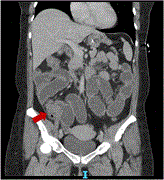

Bilateral adrenal hemorrhage after pancreaticoduodenectomy

Sarah Andres and others

Journal of Surgical Case Reports, Volume 2023, Issue 7, July 2023, rjad411, https://doi.org/10.1093/jscr/rjad411